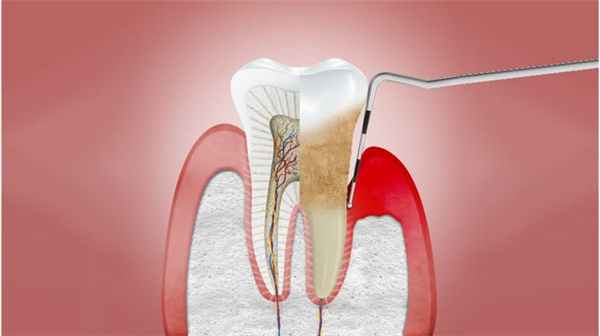

Пародонтит

Необратимое разрушение тканей пародонта в результате хронического воспаления. 2 Характеристики включают:

- Видимые признаки воспаления десен

- Кровоточивость во время осмотра с использованием пародонтального зонда или во время чистки зубов

- Разрушение соединительного эпителия и нарушение прилегания десны (образование патологического кармана и рецессия десны)

- Потеря костной ткани альвеолярного отростка

- Подвижность зуба

Это прогрессирующая болезнь десен, при которой затронута кость, удерживающая зуб, и разрушается механизм зубодесневого прикрепления. Микробы разрыхляют ткань десны, разрушают зубодесневое соединение. Зубной налет проникает все глубже, затвердевая и повреждая десну и эмаль зуба. Образуется так называемый зубной камень.

Образуется глубокий карман, который, как болото, является источником дурного запаха, неприятного привкуса во время еды. Разрыхленность тканей десны вызывает повышенную кровоточивость.

Пациенты постоянно отмечают болезненность десен, которая усиливается при приеме пищи, при малейшем давлении на десны они начинают кровоточить – все это является причиной беспокойства и раздражительности людей. При разрушении зубодесневого соединения и образовании кармана наблюдается отложение микробной бляшки на корне зуба, развитие инфицированной грануляционной ткани, рассасывание корня зуба. Начинается рассасывание кости, рецессия десны и оголение корней зубов. Это приводит к потере зуба.